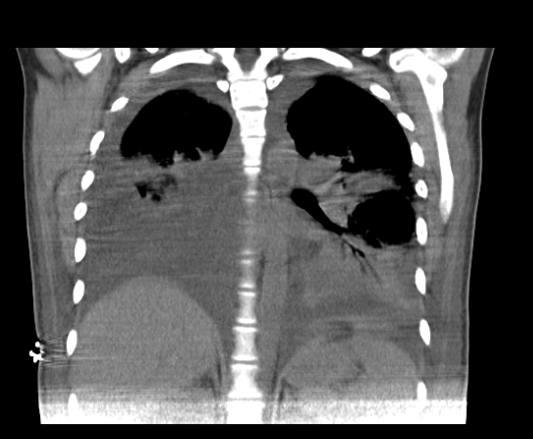

Pyelonephritis was again documented, for which the patient was hospitalized to start intravenous in-hospital antibiotic management (ampicillin/sulbactam, 3 g IV every 6 hours) and a urine culture was requested, renal and urinary tract ultrasound was performed, reporting a finding of bilateral hydronephrosis. grade II without findings of renal lithiasis or other alterations (figure 1). Patient who remained 4 days of hospitalization under antibiotic treatment mentioned above with stable evolution, however, on the 5th day of hospitalization he presented abrupt torpid evolution of his clinical picture with blood pressure figures with a tendency to hypotension, tachypnea, tachycardia (blood pressure 80/50mmHg, respiratory rate 28rpm, heart rate 112lpm, wakes up to verbal stimulation) (omSOFA: 2pts), then considering a diagnosis of sepsis of urinary origin, for which it was indicated to stagger antibiotic treatment to piperacillin/tazobactam at a dose of 4.5gr IV every 8 hours, a bolus of 2000cc (30cc/kg) was administered and basal fluids were continued at 100cc/hr; extension laboratories for sepsis were requested (Table 3) and transfer to the intensive care unit for comprehensive management was indicated. PT: prothrombin time, INR: international normalized ratio, PTT: partial thromboplastin time, CR: creatinine, LDH: lactic dehydrogenase, BUN: urea nitrogen, WBC: White blood cells, N: neutrophils, HB: hemoglobin, HTO: hematocrit, PLT: platelets. CRP: C-reactive protein, CL: chlorine, K: potassium, NA: sodium Based on platelet count findings, dengue with warning signs was considered as a differential diagnosis because it was located in an endemic area; but this diagnosis was later ruled out by both negative dengue IgG and IgM antibody tests. During her stay in the High Obstetric Risk Intensive Care Unit (seventh day of hospitalization and second day in the unit), she was assessed by the intensive medicine and critical care service, who, taking into account the intermittent fever, hypotension and systemic inflammatory response (tachycardia, tachypnea) despite management with broad-spectrum antibiotics (4 days of ampicillin/ sulbactam and two days of piperacillin/tazobactam at the doses described) and optimal fluid therapy, they consider a patient with septic shock and decide to start adjuvant therapy in the context of urinary focus shock with immunoglobulin G enriched with IgM and IgA at a dose of (5ml/kg/day) for 3 days. The patient's clinical evolution was monitored and she had persistent tachycardia (102 bpm) without tachypnea and without new febrile episodes. She was assessed by the infectious disease service (eighth day of hospitalization and third day in the unit) who considered continuing antibiotic escalation to ertapenem 1gr IV every 24 hours for 7 days due to persistent tachycardia and continuing with the last dose of immunoglobulin G enriched with IgM and IgA. The patient continued with satisfactory evolution, with blood pressure figures at goals, without requiring vasopressor support, with a progressive increase in platelet levels and improvement in the blood cell count (Table 4). On day 4 of intravenous antibiotic therapy with ertapenem (twelfth day of hospitalization, seventh day in the unit) the patient suddenly became tachypneic with saturations of 88%, for which a chest tomography was indicated (figure 2 and figure 3) where It showed a large left pleural effusion, which is why a thoracentesis was indicated, draining 620 cc of clear liquid without infectious characteristics in the bacterial culture cytology reading and a negative fungal test. Patient with immediate improvement after drainage of the pleural effusion; for which she was transferred to a general gynecological hospitalization receiving antibiotic treatment with stable vital signs, afebrile, without loss of fetal well-being evaluated by obstetric ultrasound, who completed antibiotic treatment and proposed adjuvant immunotherapy scheme with immunoglobulin G enriched with IgM and IgA with adequate drug tolerance and favorable clinical course.